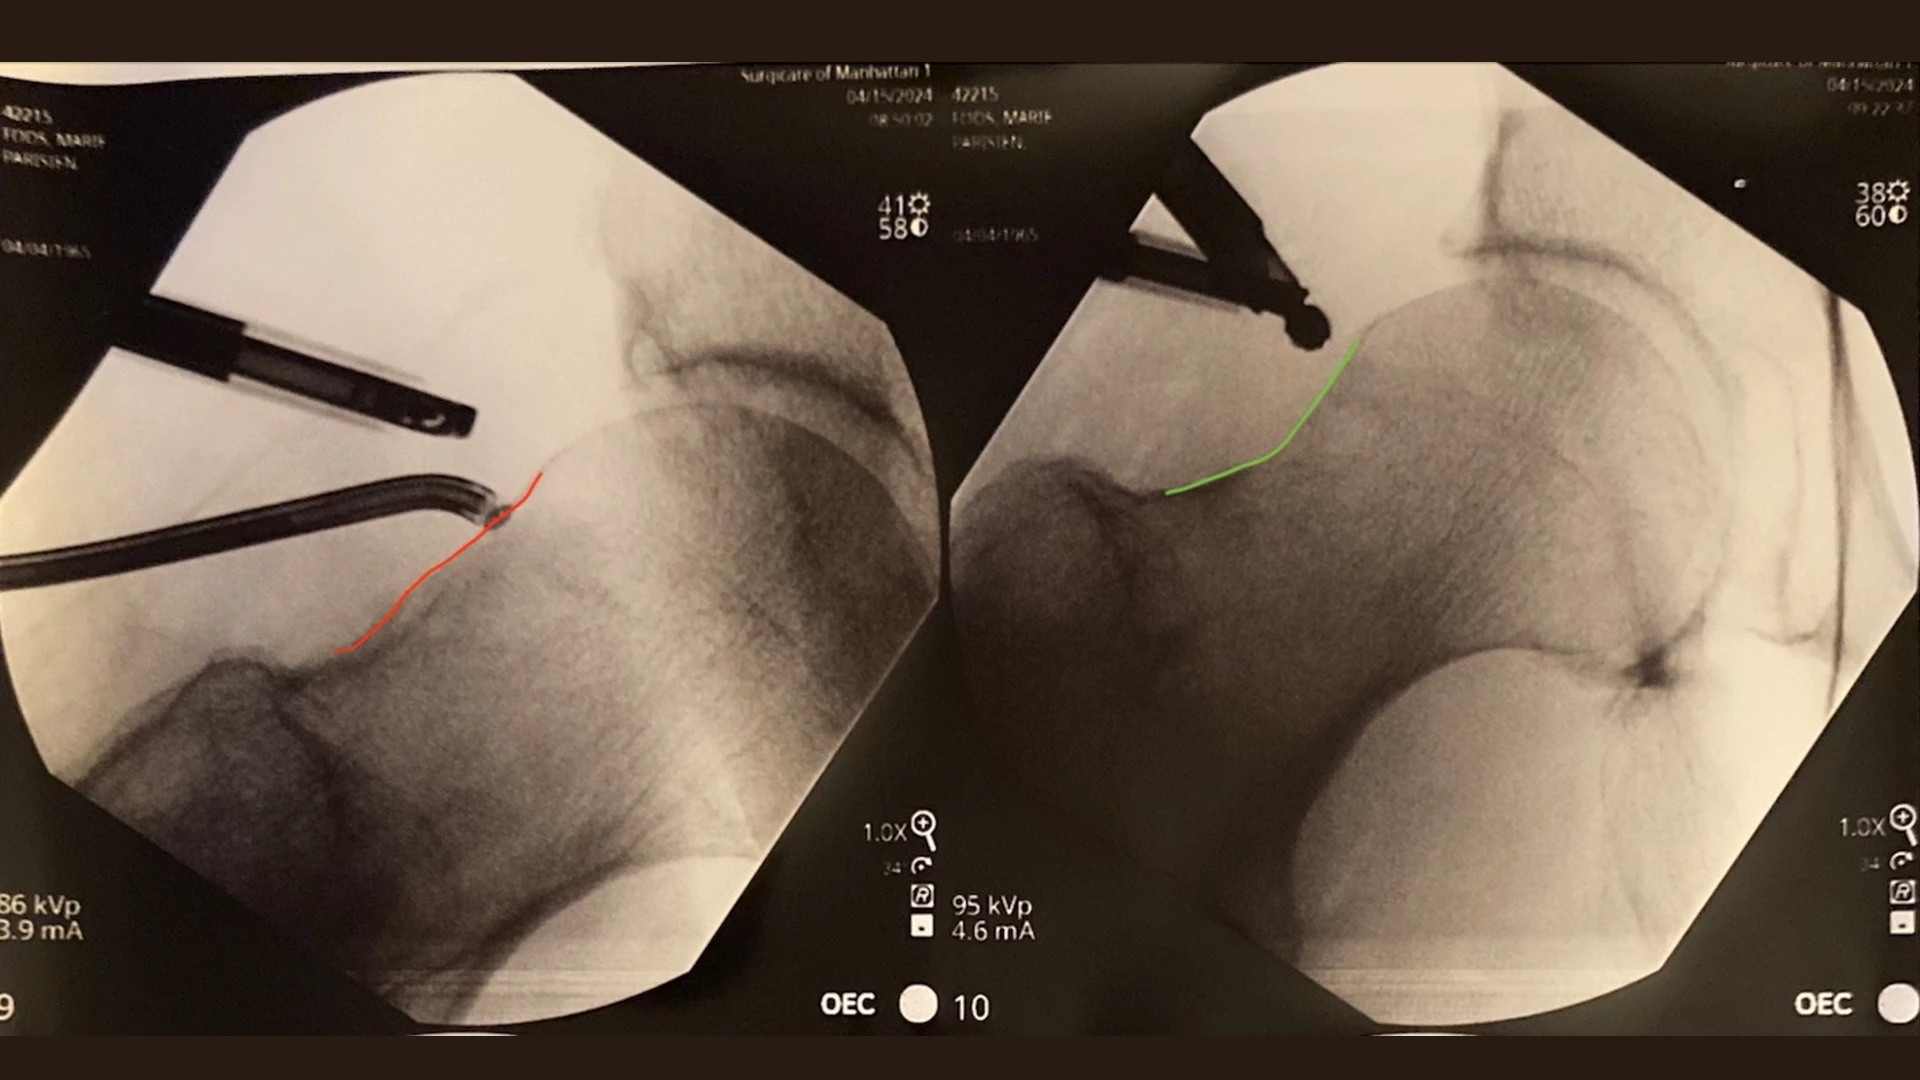

Intraoperative fluoroscopic imaging demonstrating a CAM lesion (red) and appropriate CAM resection (green).

Dr. Parisien performs hip arthroscopy as an outpatient procedure, allowing patients to go home the same day without the need to stay overnight in the hospital. Using an arthroscopic camera and small instruments, Dr. Parisien is able to perform femoral head-neck osteoplasty (shaving and contouring of the cam deformity), labral repair, complex labral reconstruction, and cartilage transplantation through tiny incisions near the hip. Patients are discharged home the same day and monitored through regular follow-up consultations at 2 weeks, 3 months, 6 months, 12 months, and 2 years post-procedure to ensure a full recovery.

Although Dr. Parisien is able to achieve superior outcomes through hip arthroscopy, he notes that the procedure poses some challenges. They include decreased visualization of the hip joint (as compared to the shoulder and knee) and the risk for traction-related complications in instances where a central perineal post is used. However, Dr. Parisien has been able to achieve a complication rate of less than half a percent through computer-assisted technology to guide surgery and a modern post-less approach.